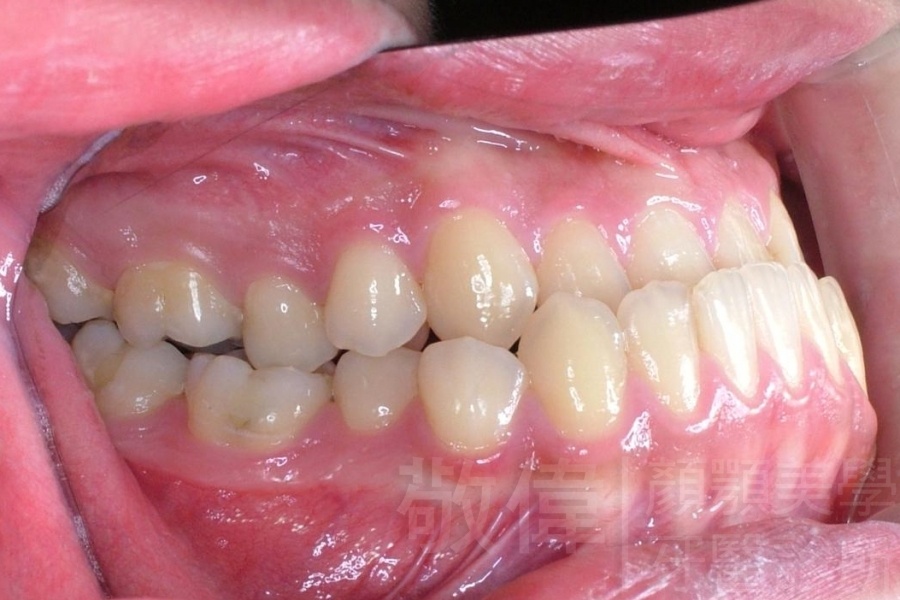

齒顏矯正/戽斗臉型 變身 大帥哥

矯正前-右   矯正前-正   矯正前-左

矯正後-右   矯正後-正   矯正後-左

<個案說明>

戽斗(學名第三級咬合 class III)矯正之後,戽斗的樣子就比較沒有了。最主要的改變是在牙齒的咬合。從側面比較,治療前、治療後的臉型 可更明顯看出來 戽斗的感覺 減少了很多。